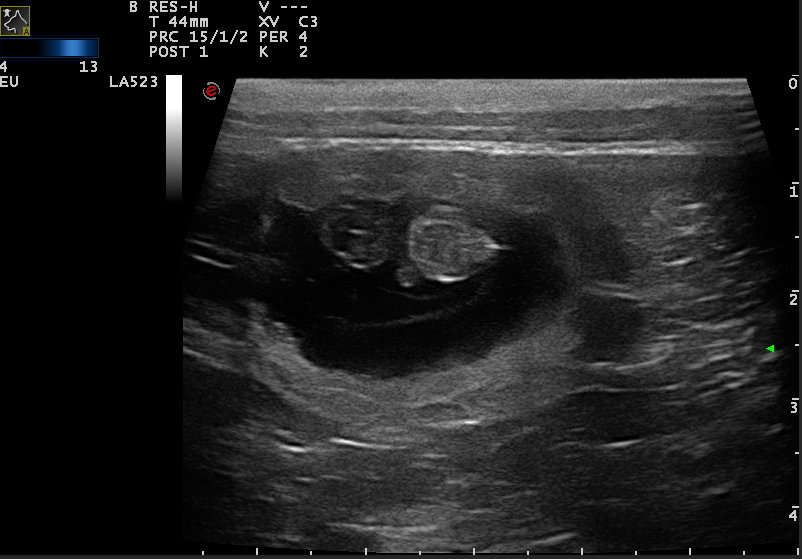

| 26 | "24-28. Tag Dies ist der beste Zeitpunkt, um die Trächtigkeit anhand des Herzschlags zu diagnostizieren. | |||

| 27 | 15,4 | 47,5 | Maple hat Übelkeit, frisst nicht | Die Embroynen sind etwas walnussgroß und sind gleichmäßig im Uterus verteilt." |